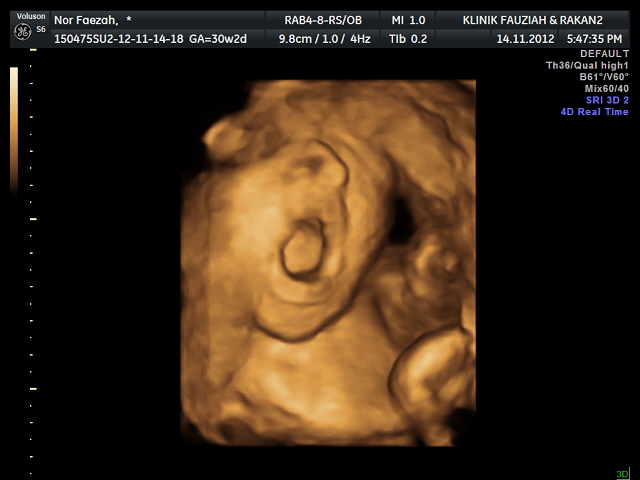

My Lil Girl in 3D 4D scanning

Syukurrrr, Alhamdulilahhhh....Maha suci mu Ya Allah :)

Buat pertama kalinya mama dan papa dapat menatap video scan baby kami di Klinik Fauziah, Jalan Ampang, Kuala Lumpur

pada

14/112012

oleh Sonografer

Dr. Jezzlyn (chinese lady)

Total: RM100 plus CD include video dan picture scan detail baby :D

Detail Baby:

Berat: 1.5 kg Normal ikut minggu

Air Ketuban: Normal

Panjang: Normal

Perasaan? Speechless!!!!! ;D Hanya mampu mengucapkan syukur alhamdulilah...

Dr. Jezzlyn seorang yang sangat peramah...disambut dengan senyuman di pintu masuk membuatkan kami terasa tenang dan damai walaupun dalam hati penuh dengan rasa gelora dan berdebar.

Ternyata ia tidak sia-sia...Allah perkenankanNya...MasyaAllah.

Anda semua sudah lihat video dan picturenya bukan?

Itulah Permata Hati kami yang akan lahir dalam 2 bulan lagi, insyaAllah :D

Video baby menguap

Menguap je keje anak mama ni..hehehe

Muka cam papa..hehehe